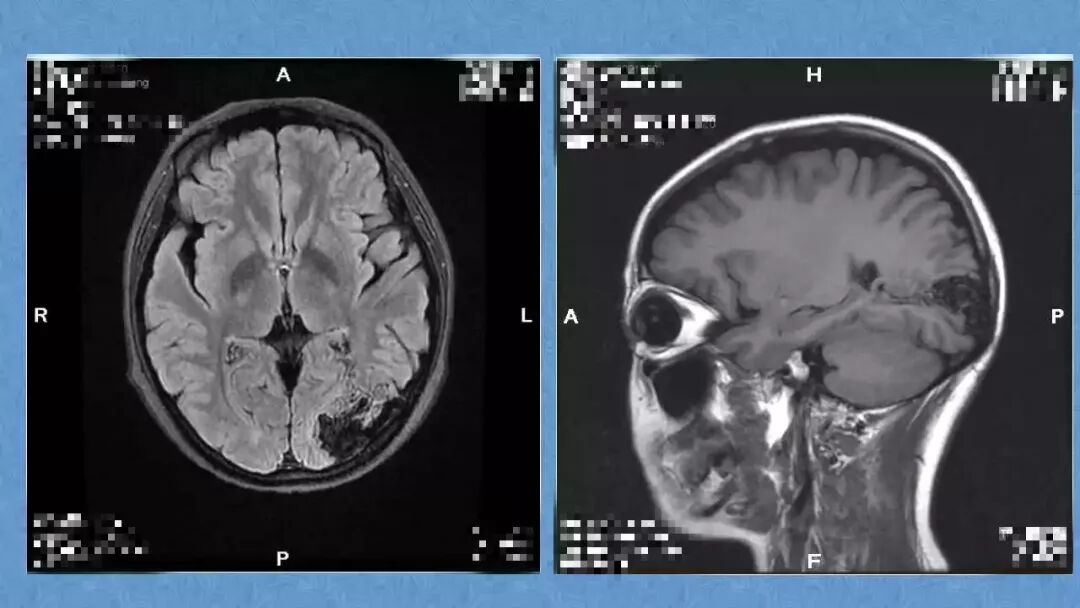

今天为大家分享的是《贝朗时间》第二十九期,湖北十堰市太和医院神经外科张力教授团队带来的:一个AVM患者的48小时纪实,欢迎阅读、分享!

张力教授:AVM切除术